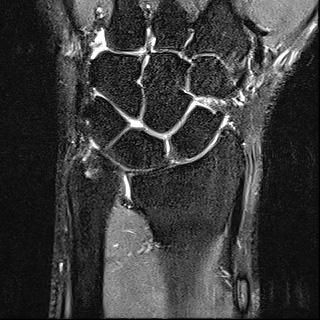

mri는 23년 부분파열 당시

• 3번 째 사진

• 제공해 주신 영상들을 확인했습니다. MRI는 2023년 부분파열 당시 촬영본이고, 단순 방사선 및 CT는 2025년 12월 골절 당시 영상으로 이해하고 검토하겠습니다.

2023년 MRI 영상을 보면, 삼각섬유연골복합체(Triangular Fibrocartilage Complex, TFCC)에 전반적인 신호 변화와 함께 척골 부착부 근처의 손상 소견이 확인됩니다. 당시 봉합술을 시행한 것은 임상적으로 타당한 판단이었습니다. 이후 경과가 양호하다가, 2025년 12월 요골·척골 원위부 골절이 발생한 점이 현재 상황의 핵심입니다.